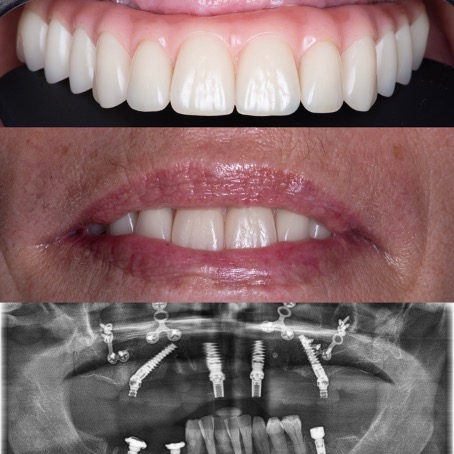

All-on-4®

Édentation totale de la mâchoire – restauration complète fixe avec des implants dentaires

Avant

Après

Le protocole All-on-4® permet de réaliser immédiatement une prothèse fixe avec seulement quatre implants par mâchoire. Les implants du fond sont mis en place avec une inclinaison de 30 à 45 degrés, dans les cas où des dents encore présentes devraient être extraites le tout est fait pendant la même opération, la journée se termine pour le patient avec l’installation des dents fixes dans le 90% des cas. Une prothèse définitive sera réalisée environ 4 mois plus tard.